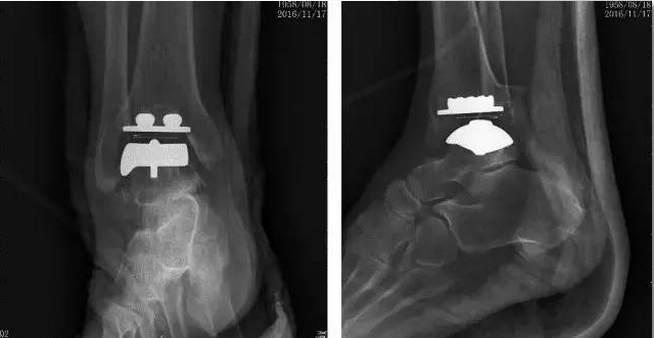

术前

蔡谞主任与清华长庚医院关节中心团队精心制定手术方案,于2016年11月15日上午成功对该患者实施了第三代踝关节假体 (STAR®LINK.)置换手术,手术力求最高精确度,过程非常顺利。完成的全踝关节假体置换位置精确,假体设计稳定牢固,踝关节内外侧软组织平衡,达到了预期的效果。术后患者恢复良好,手术取得圆满成功。患者在休养1周左右以后即可以扶拐下地行走,去除踝关节炎疼痛畸形的同时能够保留踝关节的活动度,为患者的生活和工作提供极大便利。

blob.png

术后